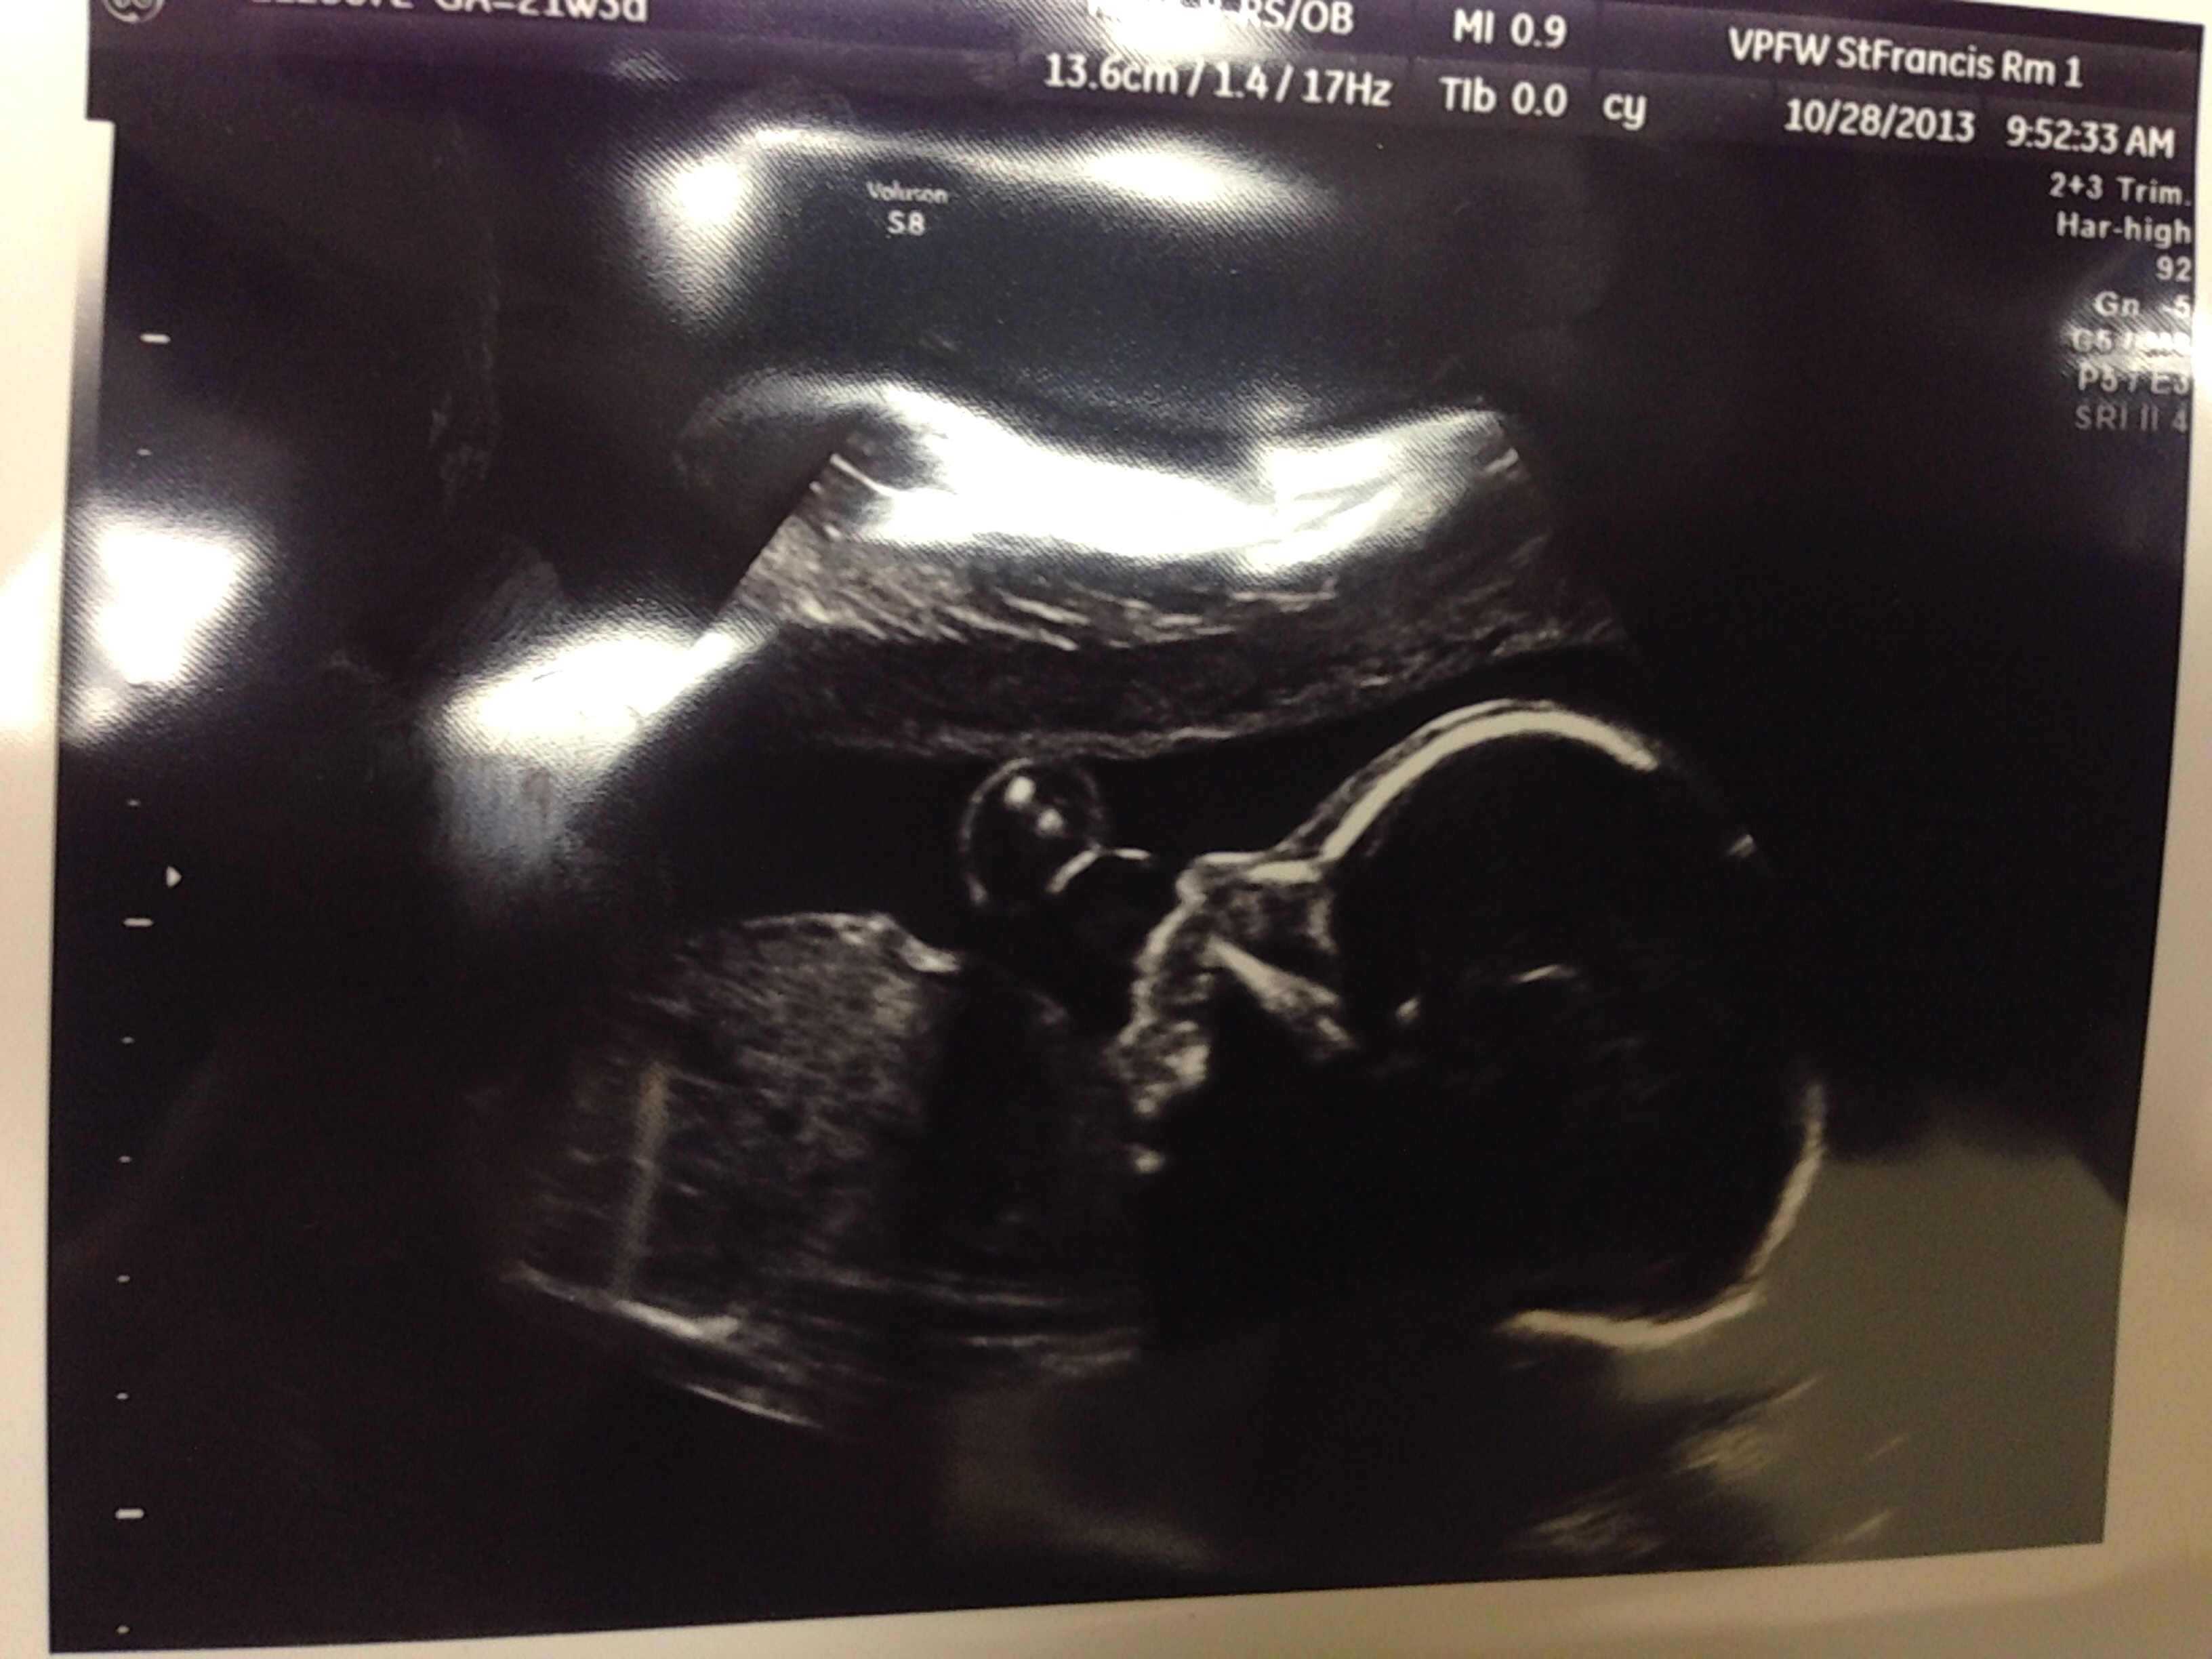

Had our anatomy scan today and it's a girl! I was convinced it was a boy though haha! Also found out that she is a little underweight for her gestational age AND I have placenta previa. Lots of news all at once! She's wriggling around in there all happy though, so no worries. Plus we get another scan in 8 weeks to look at the placenta again. Bonus! Meet Catherine Elizabeth!